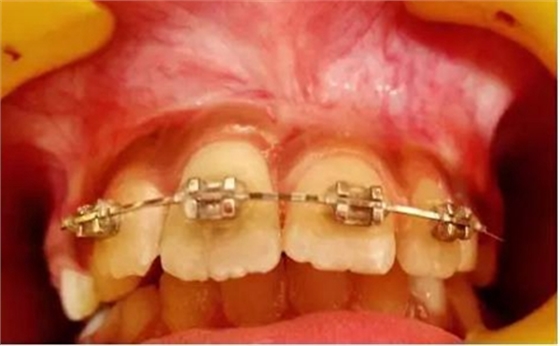

健康的 7 歲男童,前一天摔倒,上頜右中切牙和右側(cè)切牙發(fā)生挫入脫位(圖 1)。無牙外傷史,無神經(jīng)并發(fā)癥病史。檢查發(fā)現(xiàn)雙側(cè)下頜下腺增大。

口腔內(nèi)發(fā)現(xiàn):混合牙列早期,覆蓋正常,安氏I類磨牙關(guān)系。牙11和12齦緣紅腫。

牙11,12 和21對叩診敏感。牙11嚴(yán)重挫入(牙11和牙12的切緣相差7毫米),并挫入牙槽窩。與牙21相比,牙12大約挫入4毫米。